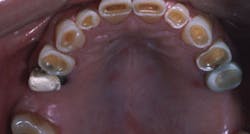

When a dentist or dental specialist becomes educated in sleep medicine and announces that their practice includes sleep medicine, many patients are interested. It is a well-known fact that 40% to 50% of people snore. This is an obnoxious condition that is offensive to anyone sleeping near the snorer, and it is known to cause many psychological and physiological problems, including marital problems. (Fig. 1) Can dentists assist in reducing or eliminating snoring? The answer is a resounding YES! Dentists are essential for this task!

- The frequency and intensity of bruxism (available from DDME Inc. mentioned above) (Fig. 4)